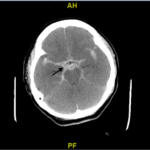

A patient presented to the emergency department (ED) as a post-coital cardiac arrest with prehospital return of spontaneous circulation (ROSC). Electrocardiogram (ECG) suggested a possible coronary artery occlusion. Given the circumstances of the arrest, computed tomography (CT) of the head was performed which demonstrated a large subarachnoid hemorrhage (SAH). Emergent percutaneous coronary intervention (PCI) was deferred due to the alternative explanation for the ECG changes and the patient’s instability. Her condition declined, and soon after the patient expired.